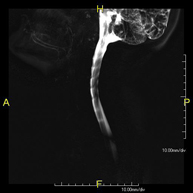

- RM Mielografía

Prueba diagnóstica no invasiva que consiste en la obtención de imágenes de alta definición anatómica de la médula espinal y las raíces nerviosas mediante el empleo de un campo electromagnético y ondas de radio (con un emisor y un receptor), así como secuencias de estudio especiales (mielográficas). No utiliza radiación ionizante. Indicaciones: hernias, compresiones medulares.

Prueba diagnóstica no invasiva que consiste en la obtención de imágenes de alta definición anatómica de la médula espinal y las raíces nerviosas, mediante el empleo de un campo electromagnético y ondas de radio (con un emisor y un receptor), así como secuencias de estudio especiales (mielográficas). No utiliza radiación ionizante. Indicaciones: hernias, compresiones medulares.